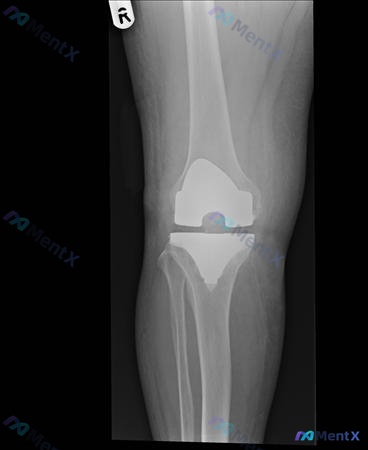

- 膝关节X光正位:假体位置/对线尚可,金属-骨界面未见明显透亮线,无明显骨溶解/破坏